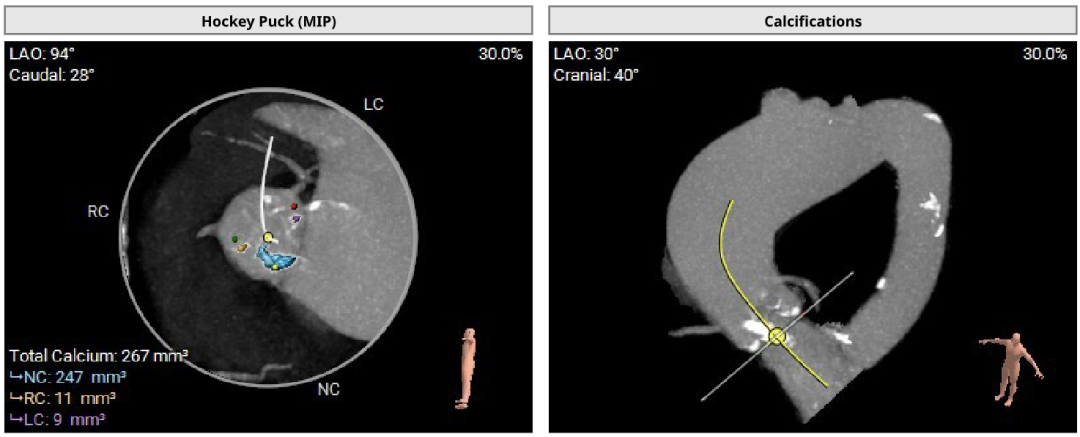

患者Type1 二叶瓣,右无融合,融合嵴钙化,钙化主要分布瓣叶缘和融合嵴处,无冠窦底钙化向下延伸至流出道4mm处。Annulus面积398mm²,LVOT面积400mm²,SOV 27.6-30.9mm,STJ高度21.3mm,内径29-32.7mm,瓣环角度62°,升主动脉扩张,左冠高度14.9mm,左冠瓣叶长度15.7mm,右冠高度15.8mm,右冠瓣叶长度9.2mm,模拟植入21#瓣膜VTC LCA 2.4mm,右侧髂内分叉处可见钙化,右侧髂外动脉最细为6.1mm,左侧髂外动脉最细为6.1mm,外周入路尚可。

850阈值下钙化积分为267mm³,钙化主要分布瓣叶缘和融合嵴,无冠窦底钙化向下延伸至流出道4mm。

释放体位 RAO 1° Cra 7° ;左冠切线 LAO 18° Cra 26°

左冠高度:High: 14.9mm

右冠高度:High: 15.8mm

左冠高度14.9mm,左冠瓣叶长度15.7mm,右冠高度15.8mm,右冠瓣叶长度9.2mm,模拟植入21#瓣膜VTC LCA 2.4mm